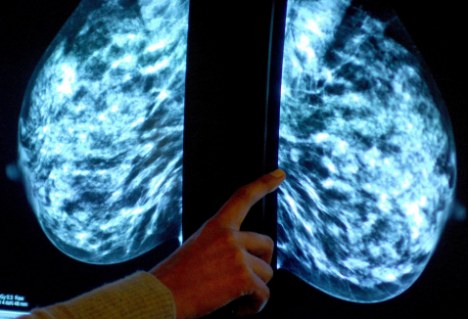

“原为寻找宇宙内超新星而设计的技术,现在正被用于癌症的诊断。”据英国《每日邮报》网站3月10日报道,天文学家现与剑桥大学的肿瘤学家组成工作小组,将曾用来区分单个恒星和遥远星系的电脑软件用于检测乳腺肿瘤的类别。

发表在《英国癌症杂志》的一篇研究报告显示,研究人员曾使用天文软件来分析2000名乳腺癌患者的肿瘤情况。报告显示,该软件可作出与人类病理学家一样准确的判断,并在某些情况下,它得出的分析更加客观。

此前,癌症细胞的分析工作是由人类病理学家通过显微镜检测组织样本来完成的。而现在的新方法是,通过化学处理癌细胞来使细胞内某些蛋白质被染成棕色,再将用高分率扫描仪建立的细胞的数字化图像传送至软件中,软件会根据细胞内棕色区域的位置来判定癌症类型。

据报告称,该项新技术可以在一天之内完成2000个样本分析,而在此之前,这需要一个病理学家团队花费一周的时间来完成。而在乳腺癌的治疗过程中,加快癌细胞分析是非常重要的,因为有些药物在有针对性地治疗某一种肿瘤时会更加有效。例如,在检测出肿瘤中含有一种特殊蛋白质后,使用赫赛汀(Herceptin)会非常有效。